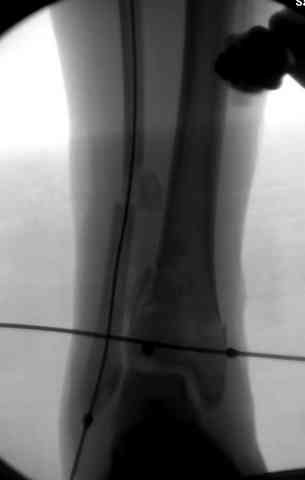

Дополнительные ренгенограммы после дистракции и

обязательная комьютерная томография дают возможности разузнать топографию расположения фрагментов, что немаловажно для планирования хирургического доступа.

По апексу фрагмента ориентируется при планировании

фиксации, также предоперационно определяется

направление фиксирующего материала: шурупа или спицы с упорной площадкой.

Первичная пластина или интрамедуллярный фиксатор на малоберцовую зависит от характера перелома, косые и многооскольчатые пластинами, а поперечных можно интрамедуллярными фиксаторами. Восстановленная длина малоберцовой служит ориентиром и помогает определению высоты большеберцовой во время восстановления.